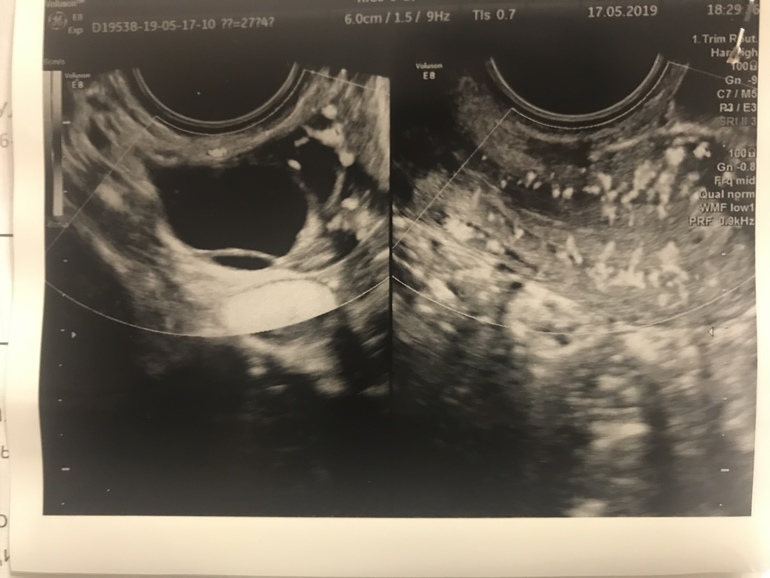

Фолликул или ЖТ?

Была два раза на фолликулометрии. Узистка сначала подумала что ЖТ, потом сказала что фолликул все так.

А я вот до сих пор сомневаюсь ( девочки, кто разбирается , на что похоже ?

1 фото) 24 мм.. если жидкость в позадиматочном пространстве в незначительном количестве

2 фото) 30,5 на 17мм , сказали уже киста